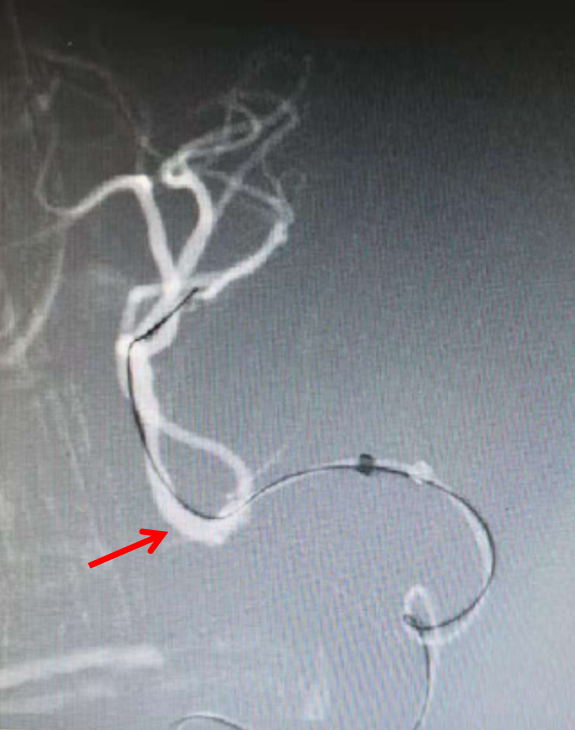

将1.5mmX10mm赛诺Neuro LPS™球囊沿微导丝引导至闭塞血管处(左图),感觉球囊稍短,分段缓慢(40秒)扩张至3atm,持续30秒后缓慢泄压后造影,可见血管部分再通(右图),但撤出球囊后前向血流不能维持。

将2.0mmX15mm的赛诺Neuro LPS™球囊沿微导丝引导至闭塞血管两端(左图),40秒缓慢扩张至3atm,持续40秒后缓慢泄压后造影,可见血管部分再通良好(右图)。